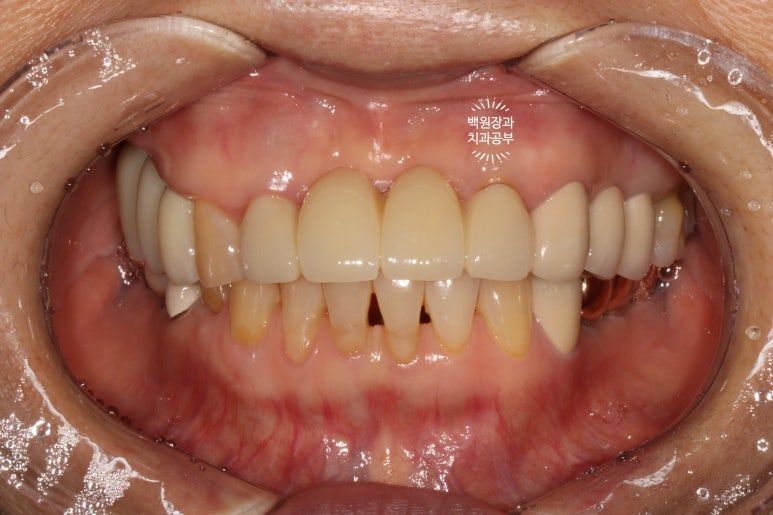

그런게 기가막힌건 그냥 입 안 사진을 봐서는 그렇게 안좋아보이지 않는다는 것입니다..

그래서 임플란트 주위염.. 임플란트 풍치는 방치되는 경향이 있습니다.

수술 전의 사진과 비교해서 생각보다 임플란트가 원래 자리와 비슷한 레벨에 위치해 있음을 확인할 수 있습니다.

정면에서 보았을 때는 잘 보이시지 않을 수 있으나,

측면에서 보았을 때, 처음에 저희 병원에 내원하셨을 때에 비해 많이 길어지지 않고 비슷한 길이의 크라운으로 제작된 것을 확인하실 수 있을겁니다.

수술 전에 비해 약 1-2mm 정도 임플란트 크라운이 길어진 느낌이네요.